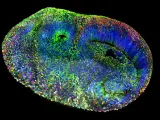

- Versiones simples y reducidas del cerebro 'in vitro' permiten estudiar posibles genes implicados en los TEA.